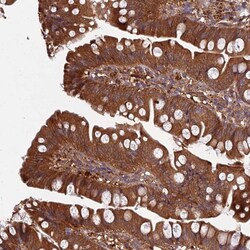

Immunogen sequence: VALTLIKQHQ ELILEATSVP DICDKFKQIT KGSFVMECHT FMQKIFSEPG SLSMATVAKL RESCR Highest antigen sequence identity to the following orthologs: Mouse - 83%, Rat - 89%.

GRTP1, also known as germ cell-specific gene 1-related protein, is a protein that is expressed in the testis and is involved in the regulation of spermatogenesis, the process of sperm cell development. It is a member of the GRP family of proteins, which are characterized by a conserved motif called the GRP domain. GRTP1 is thought to play a role in the differentiation of spermatogonia into spermatocytes and in the regulation of meiosis, the process of cell division that produces haploid cells. Mutations in the GRTP1 gene have been associated with male infertility. GRTP1 was identified as an HIV dependency factor (HDF), suggesting that GRTP1 may be an important drug target in HIV treatment.

| Applications | Immunohistochemistry (Paraffin) |